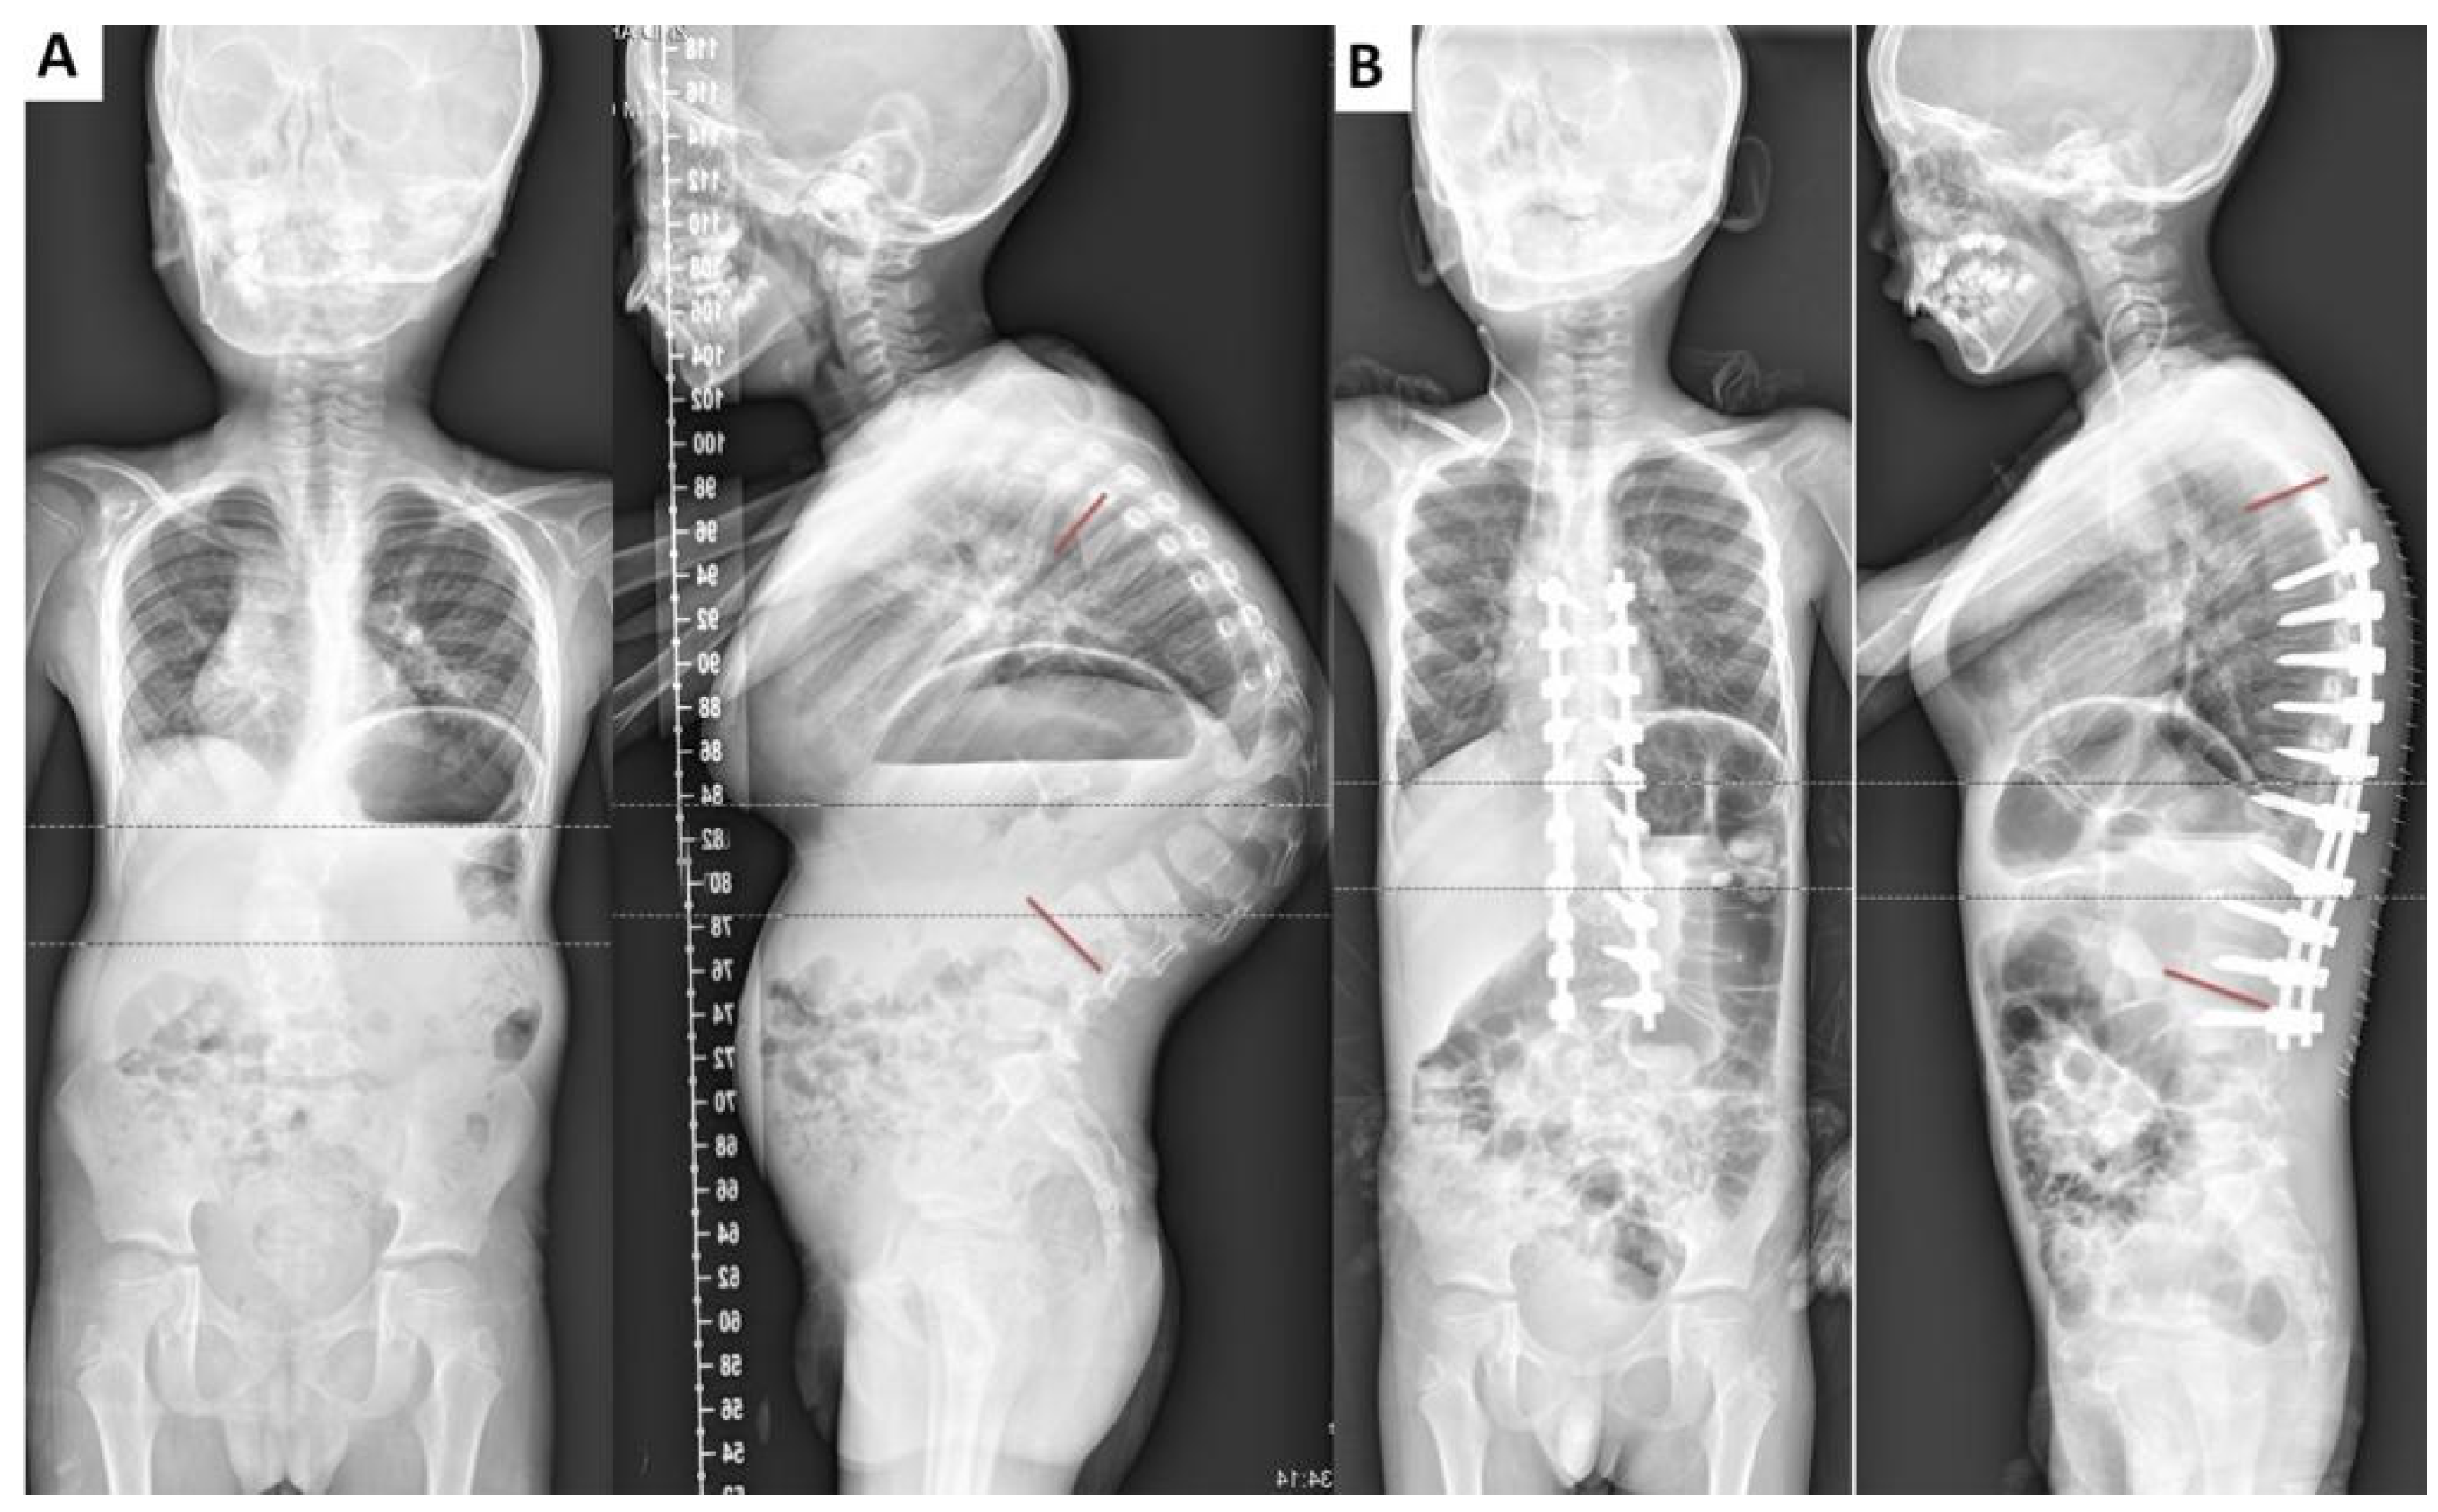

2. Case Presentation